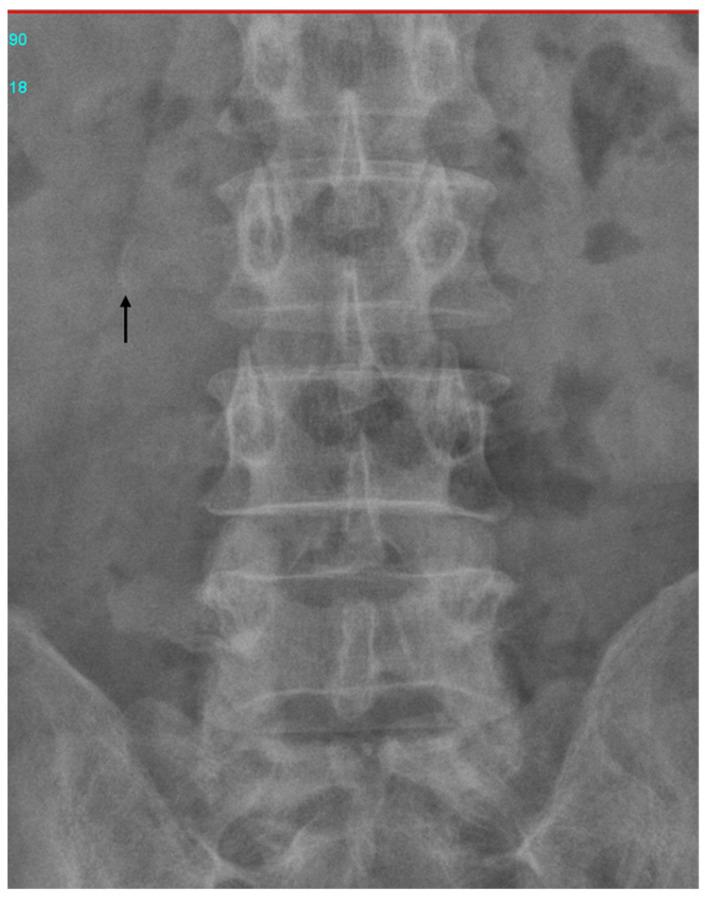

Retained surgical foreign bodies have been a cause of concern since physicians began operating on patients. Retained surgical foreign bodies in the common bile duct (CBD) are rare and may cause cholangitis and jaundice. We report the case of a patient who initially presented with fever and right upper-quadrant abdominal pain. He had received cholecystectomy and choledochojejunostomy 28 years ago and had been well since then. Abdominal computed tomography (CT) revealed left-lobe liver abscess and a linear curve of high-density material. Endoscopic retrograde cholangiopancreatography (ERCP) displayed mild dilatation of the common bile duct (CBD) and choledojejunostomic fistula of the middle CBD. A curved, linear, rusty, metallic surgical suture needle was detected and successfully removed under ERCP.

自医生开始为患者做手术以来,手术中遗留异物一直令人担忧。胆总管(CBD)内遗留手术异物较为罕见,可能导致胆管炎和黄疸。我们报告一例患者,最初表现为发热和右上腹疼痛。他28年前接受过胆囊切除术和胆总管空肠吻合术,此后一直状况良好。腹部计算机断层扫描(CT)显示左叶肝脓肿和高密度物质的线性曲线。内镜逆行胰胆管造影(ERCP)显示胆总管(CBD)轻度扩张及胆总管中部空肠吻合口瘘。检测到一枚弯曲、呈线性、生锈的金属手术缝合针,并在ERCP下成功取出。